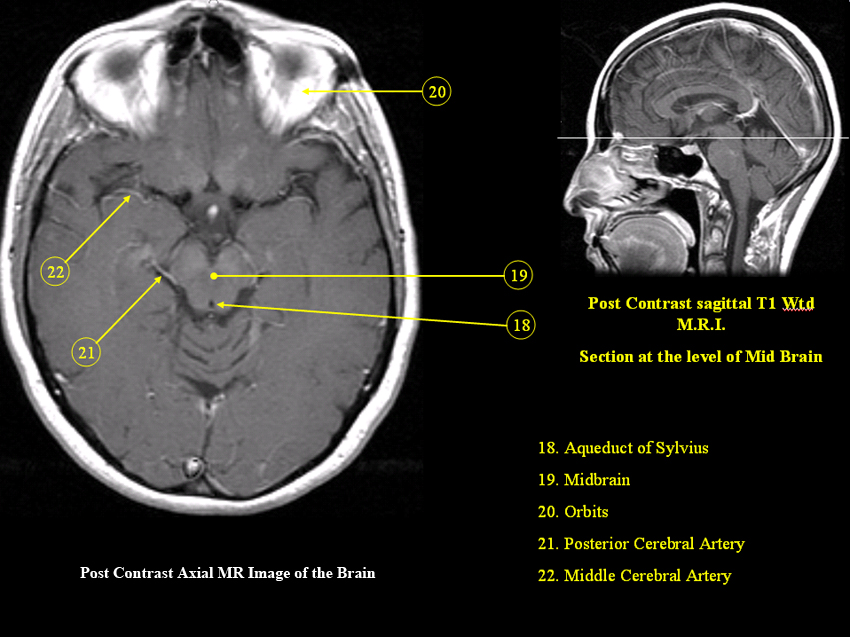

MR Brain and Spine